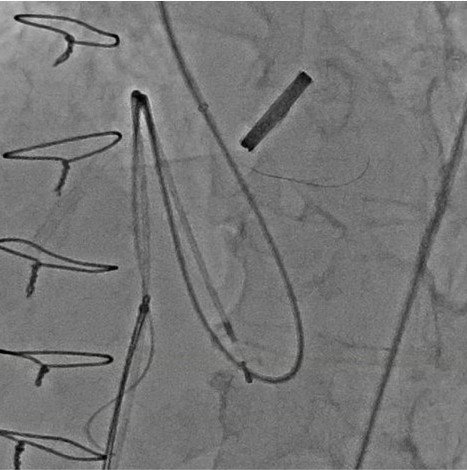

We performed this procedure under generalanesthesia with TEE. The first step was to close the VSP so that we manipulateda 5 Fr. Destination sheath with diagnostic JR4 catheter as mother and childtechnique. Inside of the system, 0,014-inch wire and microcatheter was advancedleft ventricle(LV) from aortic PVL. We turned the wire inside LV to access theVSP. We succeeded to have the wire advance to right ventricle(RV) through the LVand PVL. The next step was creating AV loop so that the 0.014 wire was snaredin the pulmonary artery and pulled out from right femoral vein. After creatingAV loop with 0.014 wire, the loop was exchanged to 0.035 wire and AMPLATZERDuct Occluder 6/4 was implanted into VSP. After closing VSP, we accessed insidethe PVL again and the wire was switched to super stiff one to advance theDestination sheath inside LV. Once the sheath was advanced in LV, 8mm AMPLATZERvascular plug 2 was deployed to close the PVL.